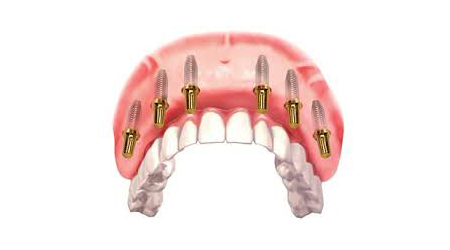

Dental Implants

Raising Face Value Through Perfect Teeth

• Immediate Implants

Swift Smile in 3 Days

• 3 Months Implants

Conventional Implants

Full Mouth Rehabilitation with 6-8 Implants Protocol for good bone

Upper Jaw/Lower Jaw (Per Jaw)- NOBEL BIOCARE

Technique INR US

6-8 NOBLE BIOCARE Implants + 12 to 14 Units Metal Ceramic Bridge (Porcelain Fused to Metal 350000 5400

6-8 NOBLE BIOCARE Implants + 12 to 14 Units ZIRCONIUM (Metal Free) CERAMIC BRIDGE 500000 7600